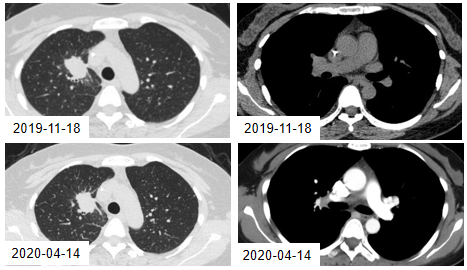

2019年11月27日,患者接受奥希替尼二线治疗,在治疗过程中,肺部原发病灶略缩小、肝脏转移病灶持续稳定。

图4. 2019年11月18日与2020年4月14日的CT检查结果

2020年8月31日,CT检查提示:肺部病灶、肝脏病灶均较前明显增大,考虑奥希替尼耐药,无进展生存期(PFS)为9.1个月。

图5. 2020年4月14日与8月31日的CT检查结果